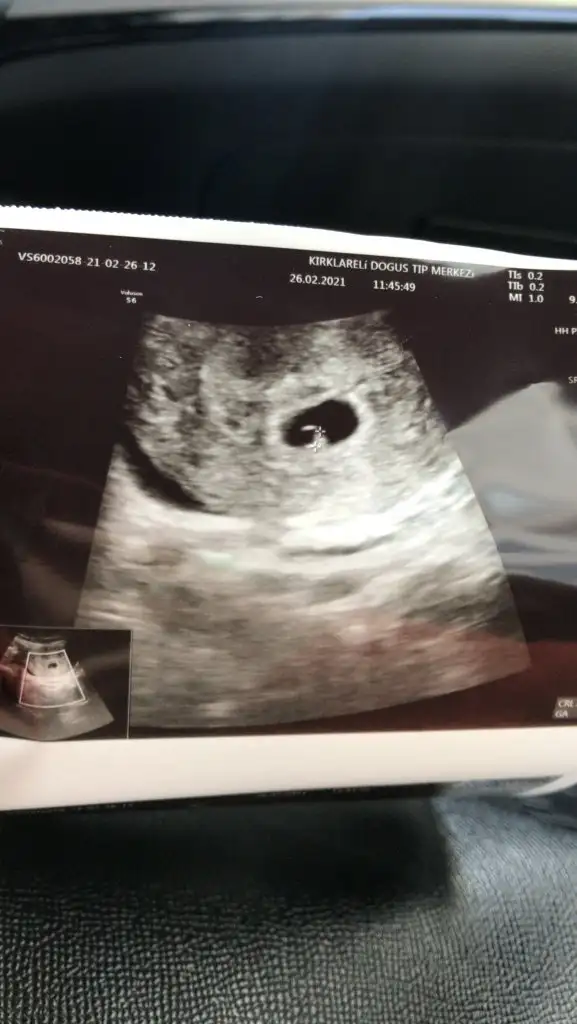

Maşallah canım çok sevindim sağlıcakla ilerlesin kucağında gör inşallah bebeğini hadi gözün aydınKızlar çoook şükür kalp atışını duydukbu sesi duyana kadar hep içimde korkular endişeler vardı hamileyim diyemiyordum kendi kendime benimsemekten korkuyordum .. hala da öyle ama çook şükür dünyanın en güzel sesiymiş bu hala kalbim ağzımda ağlayıp duruyorum.. Allahım isteyen herrkkese nasip etsin inşallah tez zamanda ve hamile olanlara sağlıkla kucağımıza almayı nasip etsiin amiin

MaşallahhGözün aydın canım masallahçok şükür binlerce kez şükürler olsun Bakalım bundan sonra ikili testler sonra cinsiyetler öyle devam edicek inşallah sağlıkla